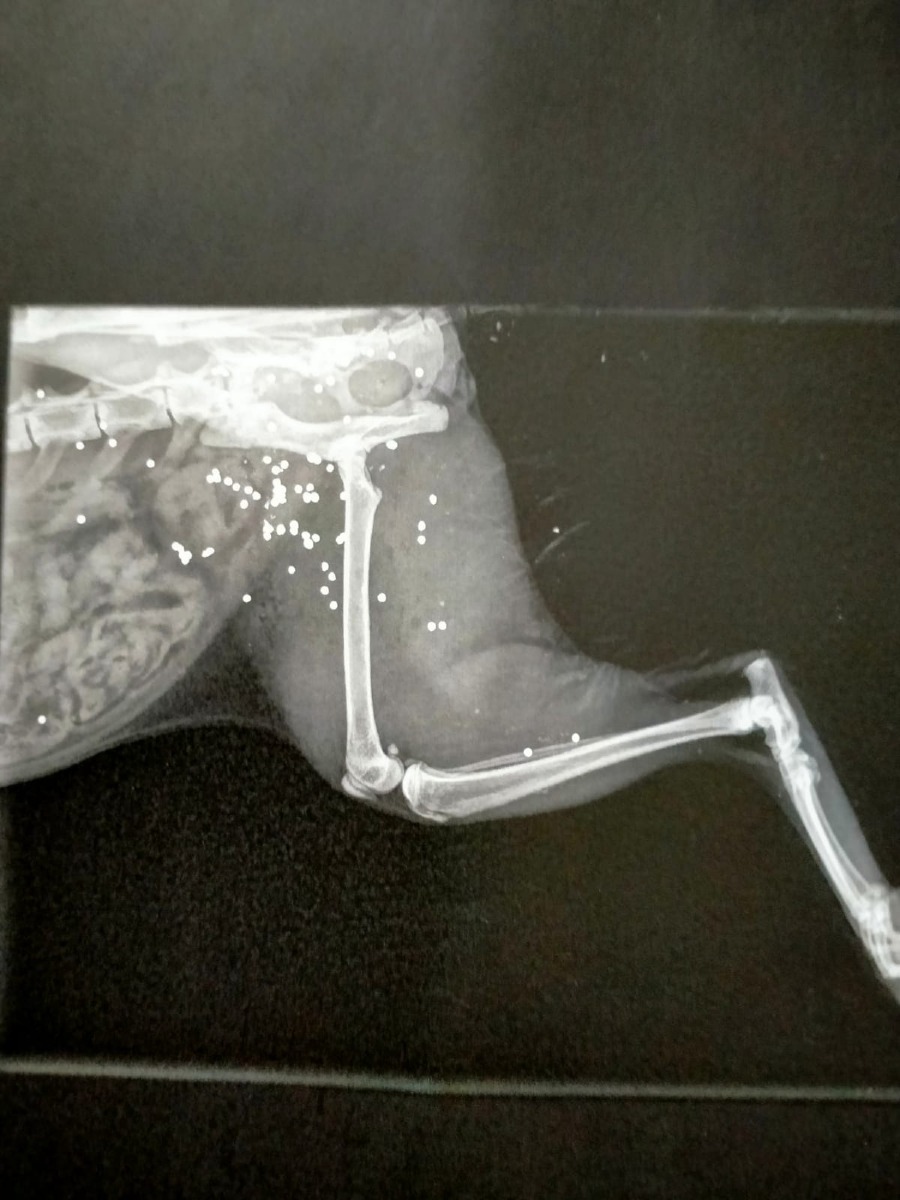

La famiglia, accortasi immediatamente della gravità della situazione, ha portato l’animale presso una clinica veterinaria della zona. Qui, a seguito degli accertamenti clinici, è emersa la causa delle ferite: la gatta era stata colpita da pallini sparati da un fucile da caccia.

Un gesto che, oltre a provocare gravi sofferenze all’animale, solleva forti preoccupazioni anche sul piano della sicurezza pubblica. L’utilizzo di armi da fuoco in prossimità di abitazioni o centri abitati rappresenta infatti un comportamento estremamente pericoloso, con possibili conseguenze anche per le persone.